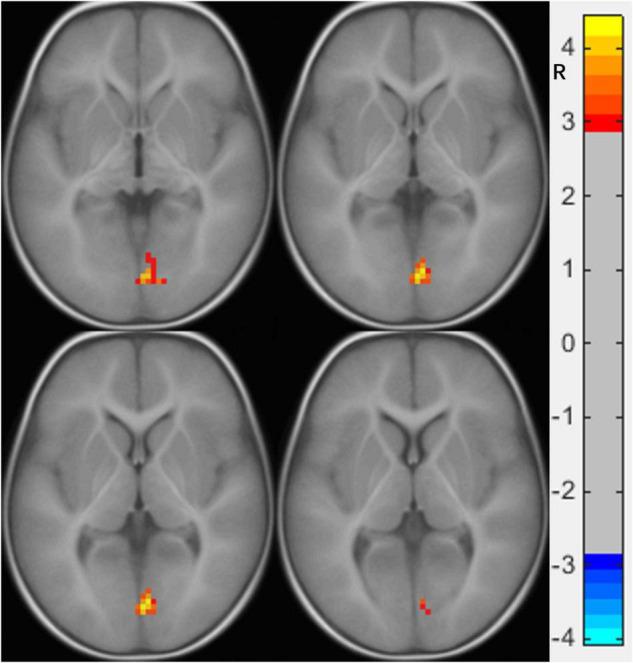

Individuals with ASD showed enhanced FC between the right calcarine and the right lingual gyrus (LG). The right medial orbital frontal cortex also showed increased FC with bilateral inferior temporal gyrus (ITG) [two-tailed, voxel-level < 0.001, gaussian random field (GRF) correction, cluster-level < 0.05]. We did not find a correlation between the abnormal FC value and clinical scales.

患有ASD的个体在右侧距状沟和右侧舌回(LG)之间显示出增强的功能连接。右侧眶额内侧皮质与双侧颞下回(ITG)之间的功能连接也增加了[双尾,体素水平<0.001,高斯随机场(GRF)校正,簇水平<0.05]。我们未发现异常功能连接值与临床量表之间存在相关性。